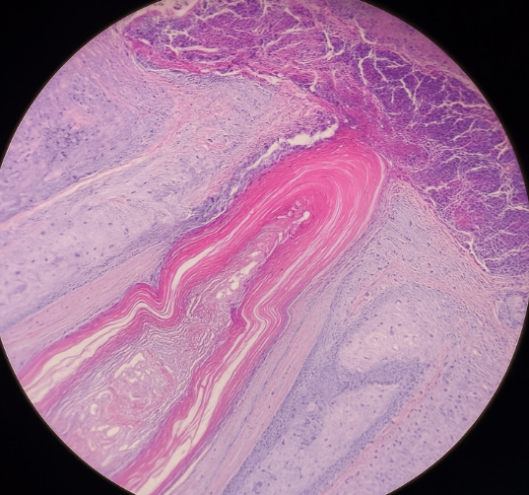

为了明确诊断,医生为患者安排了皮肤活检,而皮肤病理结果给出了确凿的证据(图2):

图2:组织病理示扩张的毛囊漏斗部充满角质物及炎性碎屑

显微镜下显示:鳞状上皮伴有棘皮症和角化过度,覆盖着厚厚的纤维蛋白-白细胞壳、含有中央角膜栓的滤泡漏斗,以及富含中性粒细胞的滤泡周围淋巴浸润。同时,皮损

处的细菌培养检出了甲氧西林敏感的金黄色葡萄球菌